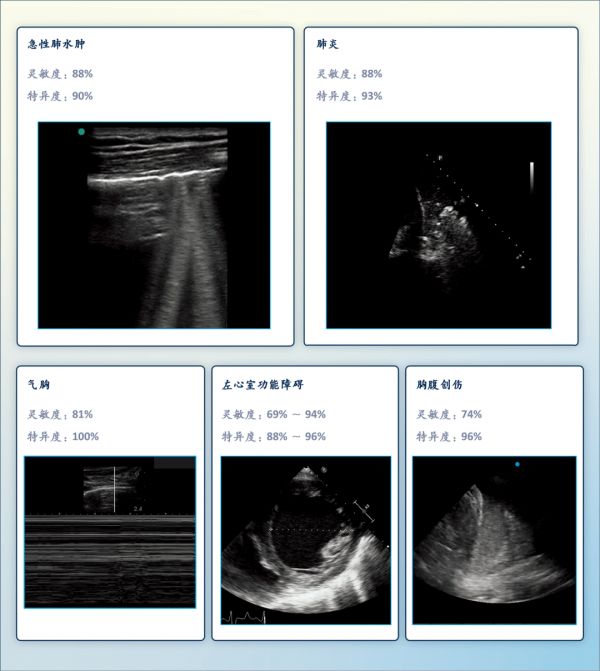

图2. POCUS对常见疾病的诊断准确度

POCUS可有效且安全地诊断急性肺水肿、肺炎、气胸、左心室功能障碍和胸腹创伤。